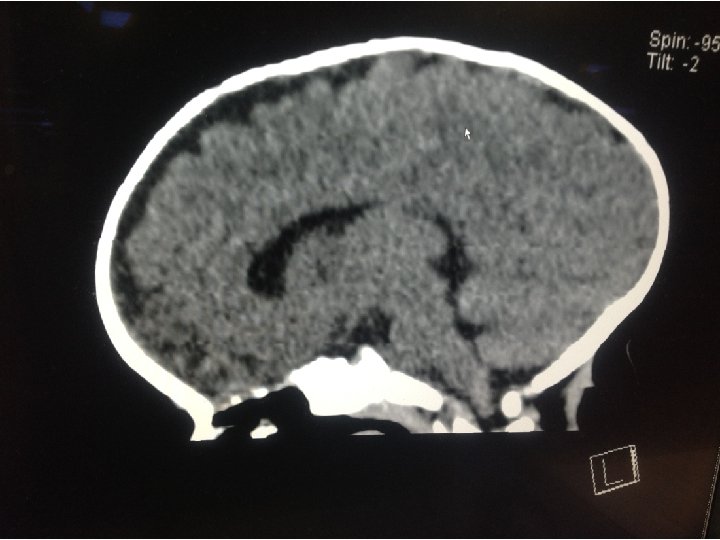

WORK UP • Basic labs • CBC, CMP, PT, INR, PTT • CT Head

SOOOO…. . ? • CT shows scaphocephaly, but normal ventricles. • No acute neurosurgical concerns • Primarily sent for nystagmus • Could the nystagmus be anything else?